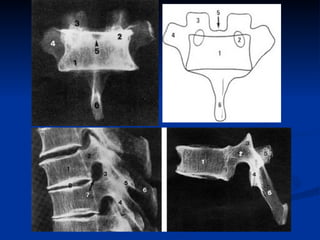

Rappel anatomique Vertèbre fondamentale: Corps:  2/3 d’un cylindre Arc postérieur: Amarré au corps par les  2 pédicules. 2 lames  au niveau postérieur prolongées par  l’apophyse épineuse   2 apophyses transverses  latéralement 2  apophyse articulaires supérieures  et  2  inférieures  aux deux extrémités d’une colonnette osseuses intercalée entre le pédicule en avant, la lame en arrière La partie moyenne de cette colonnette:  isthme

Image radiologique de face Corps vertébral:   Rectangulaire rapport constant hauteur/largeur = 2/3 Limites supérieures et inférieures planes: plateaux Pédicules :   Yeux vides regardant bien de face Apophyse épineuse:   Nez au milieu de la figure Rappel anatomique

Image radiologique de face Apophyses transverses : bras écartées Lames :  bande claire horizontale  ±  rétrécie en son milieu en superposition avec l’ombre du corps vertébral. Apophyses articulaires  sup. et inf. : cornes épaisses

Image radiologique de profil: Corps vertébral en avant: Rectangulaire, Bord postérieur épaissi: projection du mur postérieur Apophyse épineuse en arrière mince donc peu lisible Entre corps vertébral et apophyse épineuse se projettent en superposition: Les pédicules droits et gauches Les apophyses articulaires  et les colonnes postérieures  en partie constitués par l’isthme

Rappel anatomique Vertèbrefondamentale: Corps: 2/3 d’un cylindre Arc postérieur: Amarré au corps par les 2 pédicules. 2 lames au niveau postérieur prolongées par l’apophyse épineuse 2 apophyses transverses latéralement 2 apophyse articulaires supérieures et 2 inférieures aux deux extrémités d’une colonnette osseuses intercalée entre le pédicule en avant, la lame en arrière La partie moyenne de cette colonnette: isthme

Image radiologique deface Corps vertébral: Rectangulaire rapport constant hauteur/largeur = 2/3 Limites supérieures et inférieures planes: plateaux Pédicules : Yeux vides regardant bien de face Apophyse épineuse: Nez au milieu de la figure Rappel anatomique

Image radiologique deface Apophyses transverses : bras écartées Lames : bande claire horizontale ± rétrécie en son milieu en superposition avec l’ombre du corps vertébral. Apophyses articulaires sup. et inf. : cornes épaisses

Image radiologique deprofil: Corps vertébral en avant: Rectangulaire, Bord postérieur épaissi: projection du mur postérieur Apophyse épineuse en arrière mince donc peu lisible Entre corps vertébral et apophyse épineuse se projettent en superposition: Les pédicules droits et gauches Les apophyses articulaires et les colonnes postérieures en partie constitués par l’isthme